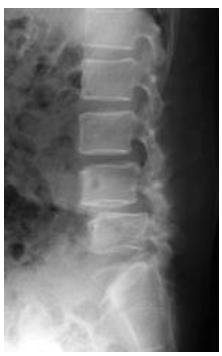

腰骨のレントゲンです。 第4腰椎にすべり症を認めます。おそらく第4腰椎と第5腰椎間で神経の圧迫を来していることは推定できるのですが、実際の神経の圧迫形態は分かりません。